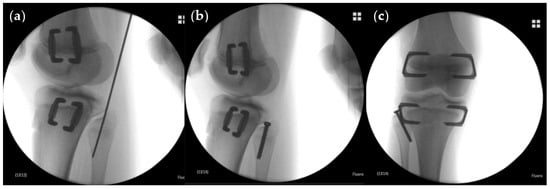

2.2. Indication, Operative Technique, and Applied Implants

2.3. Implants Applied for Epiphysiodesis